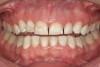

Figure 2  Asymmetric tooth wear in a bruxism triad patient as a result of friction from bruxing, poor salivary lubrication as a byproduct of medication, and roughened surfaces created as a result of erosive reflux.

Figure 2